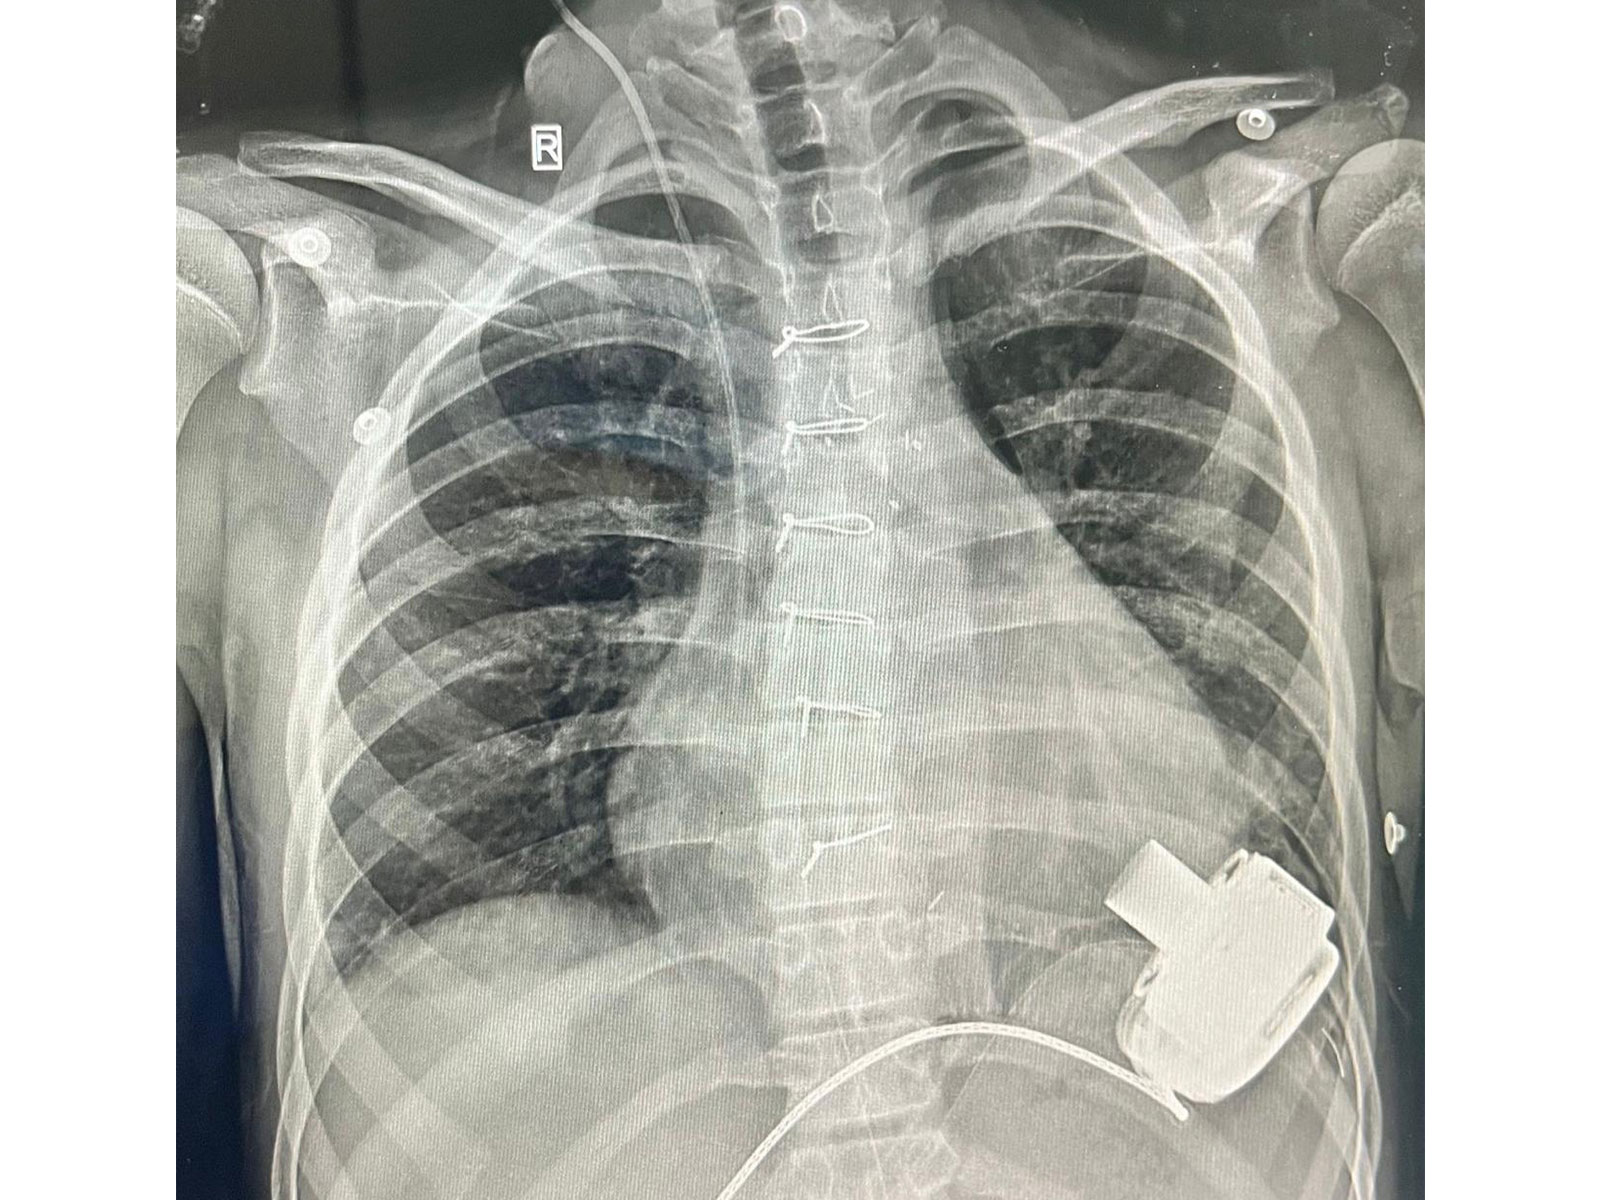

This 14-year-old boy is now the first child to be discharged in Northern India after receiving a Mechanical Heart- A Left Ventricular Assist Device. He is now also the youngest recipient of an LVAD device in India. This pioneering surgery was performed at the Department of Pediatric Cardiac Surgery at a Private Hospital in Gurugram.